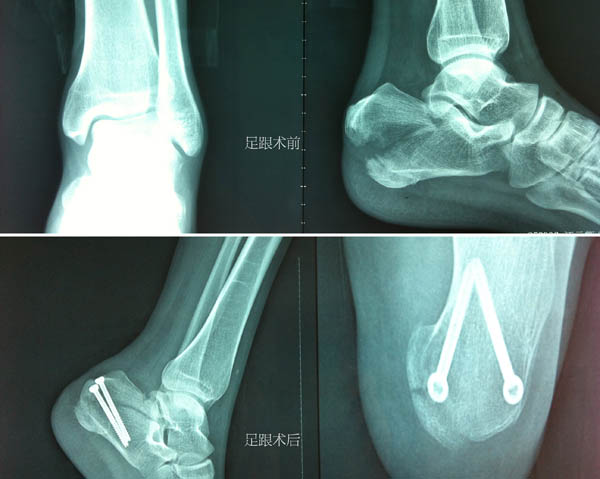

术后肢体功能图

足跟术前后

解除了肘关节的恐怖现象后,董谢平着手逐一进行进行腕舟骨和跟骨的复位内固定。骨折的微创治疗是董谢平主任的拿手戏,与其讲董谢平主任水平高一些,还不如说他更认真负责一些。他以娴熟的手法复位骨折后,在进针点皮肤处戳一小切口,并在C形臂X线机的监视下经皮钻入细钢针,再沿细钢针拧入空心螺丝钉,完成了损伤小、花费少、恢复快的舟骨和跟骨骨折微创复位内固定术。